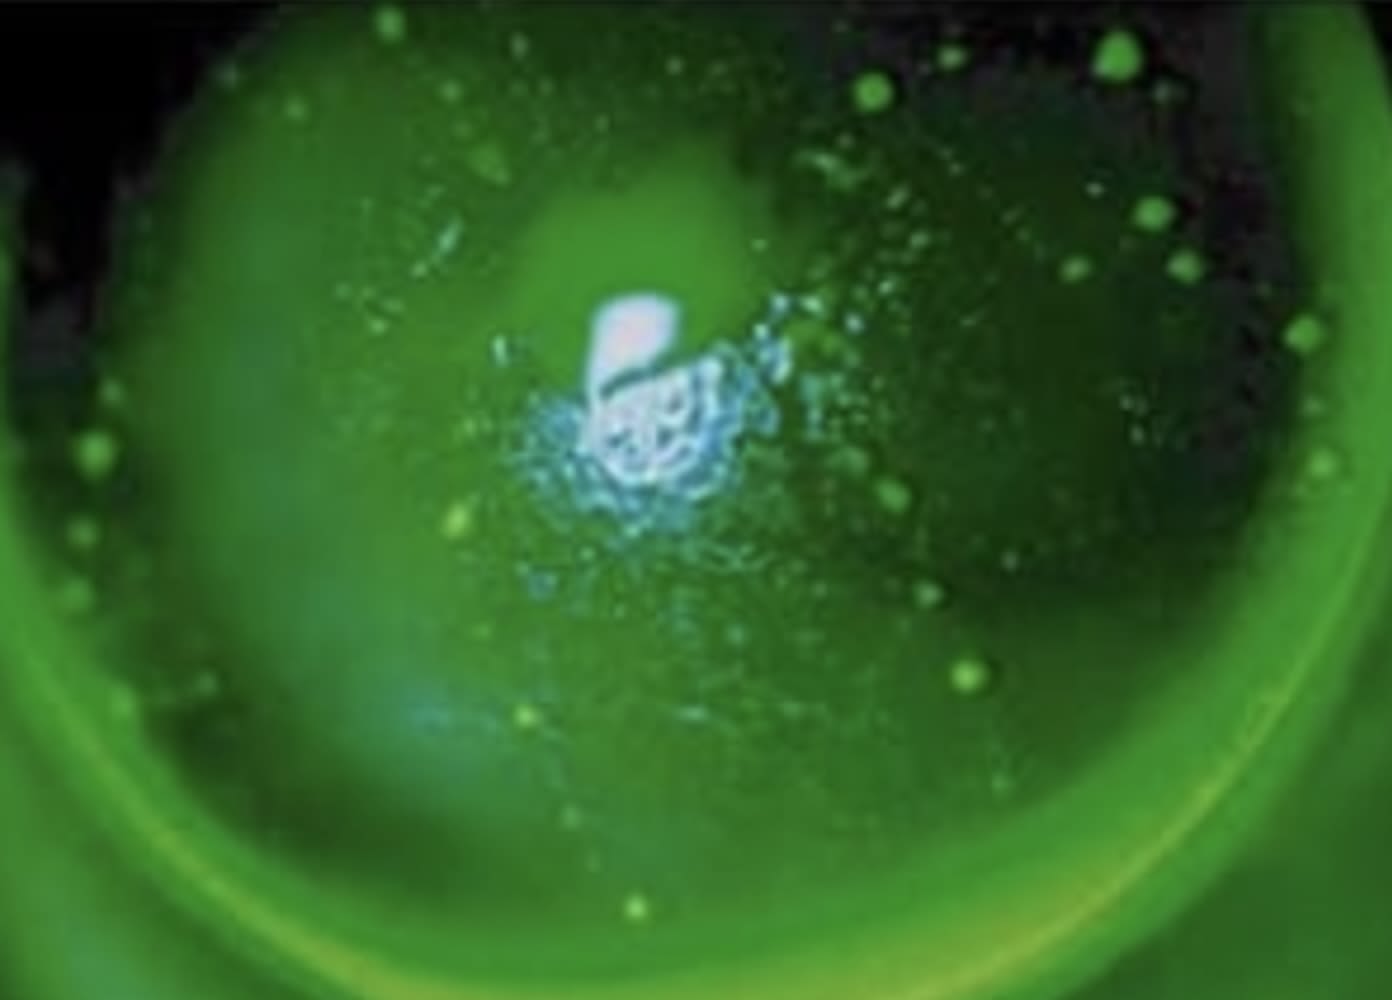

Ocular surface evaluation revealed a tear breakup time of nine seconds in both eyes without significant corneal or conjunctival staining. Indirect illumination slit lamp evaluation showed mild central corneal edema in both eyes.